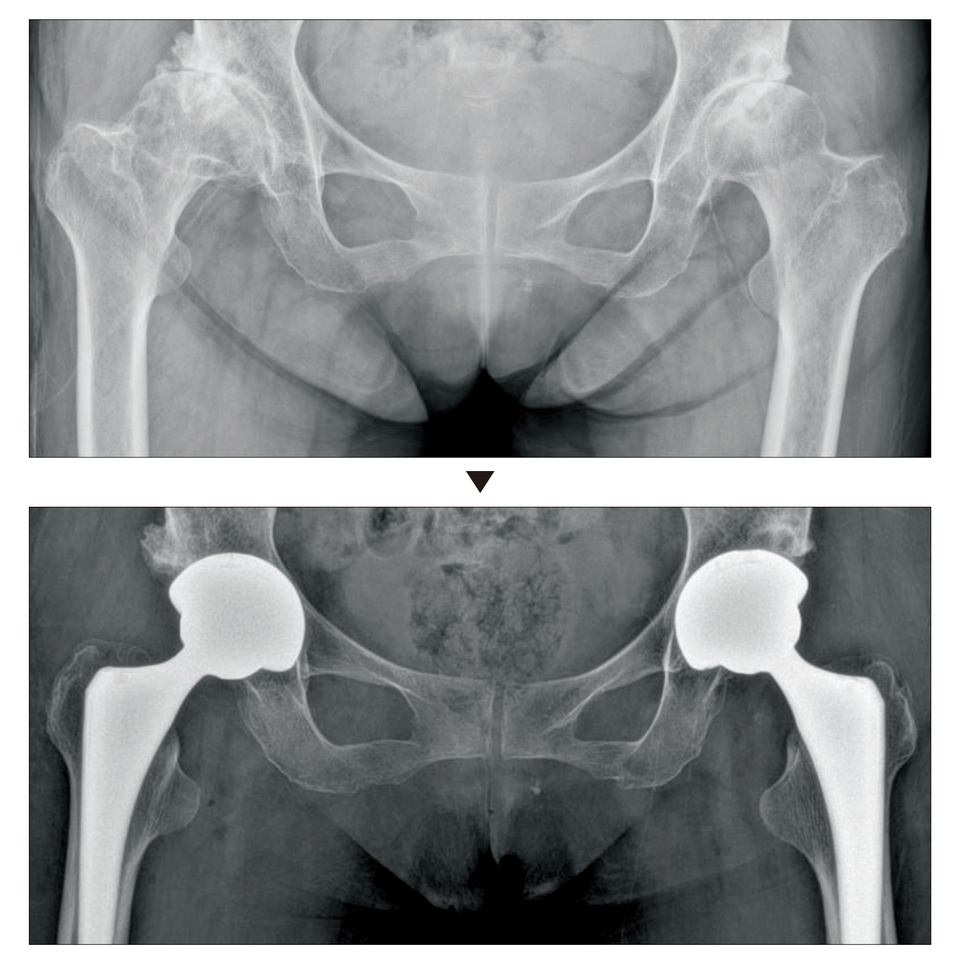

- 인공관절 치환술: 가장 일반적인 고관절 수술입니다. 퇴행성 관절염이나 심한 외상으로 인해 고관절이 손상된 경우, 인공 관절로 대체합니다. 이 수술은 대개 1-2시간 가량 소요되며, 회복이 길어질 수 있습니다.

- 진단적 검사: 의사가 필요할 경우 정기적으로 X-ray나 MRI를 통해 관절의 상태를 체크할 수 있습니다.